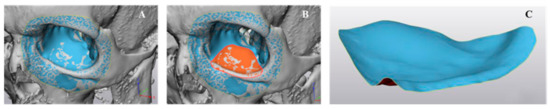

2.1. Medical Image Processing and Modeling of Patient-Specific Orbital Implants